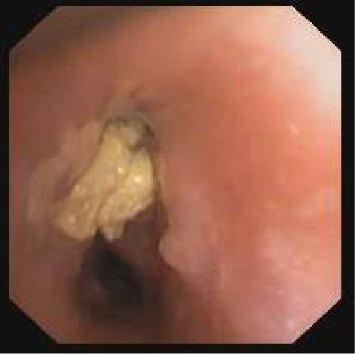

Eikenella corrodens is a commensal bacterium of the buccal cavity and rarely causes lower respiratory infections in healthy children. Two young patients with persistent pleuropneumonia caused by E. corrodens are presented. In both cases, an obstructing endobronchial foreign body was found. Removal of the foreign bodies allowed complete recovery. A local and literature review demonstrated E. corrodens causing empyema in only four other cases, all with comorbidities. We conclude that in cases of persistent pneumonia in healthy children due to Eikenella corrodens, an aspirated foreign body should be suspected.